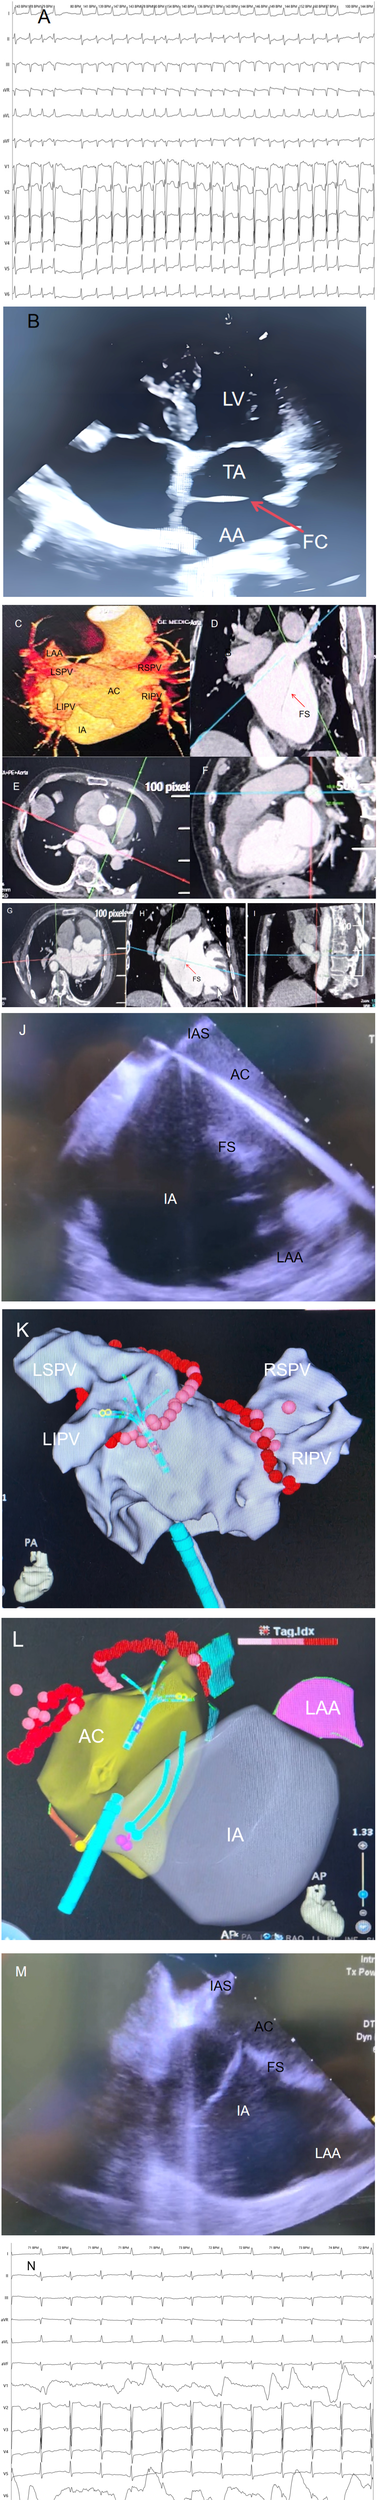

The preoperative ECG showed persistent AF with a ventricular rate of approximately 143 bpm, disappearance of P waves replaced by f waves, and absolutely irregular RR intervals; Electrocardiogram (ECG) revealed left axis deviation, ST-segment depression in multiple leads, and T-wave flattening with inversion (Figure 1A).

(A) Preoperative electrocardiogram (ECG) of the patient showing atrial fibrillation. (B) Transthoracic echocardiography (TTE) clearly visualizes the fibromuscular septum (FS), Intrinsic Atrium (IA), and Accessory Atrial Chamber (AC) in the patient. (C–I) Contrast-enhanced cardiac computed tomography (CE-CT) and 3D reconstruction of the patient, demonstrating the structural characteristics of cor triatriatum from multiple angles. The Accessory Atrial Chamber (AC) is connected to all four pulmonary veins (PVs), while the Intrinsic Atrium (IA) is connected to the left atrial appendage (LAA). (J) Intracardiac Echocardiography (ICE)-guided transseptal puncture to access the Accessory Atrial Chamber (AC). (K) Pulmonary vein antrum isolation (PVI) performed under guidance of the Johnson & Johnson Cato 3D mapping system. (L) Intracardiac Echocardiography (ICE) modeling illustrating the anatomical relationships: the Accessory Atrial Chamber (AC) is connected to all four pulmonary veins (PVs), and the Intrinsic Atrium (IA) is connected to the left atrial appendage (LAA). (M) Intracardiac Echocardiography (ICE)-guided catheter traversal across the fibromuscular septum (FS) into the Intrinsic Atrium (IA). (N) Following pulmonary vein isolation (PVI), cardioversion with a 150-J shock was performed, converting the patient to sinus rhythm with a heart rate of 71 beats per minute (bpm). IA, intrinsic atrium; AC, accessory atrial chamber; FS, fibromuscular septum; IAS, interatrial septum; LIPV, left inferior pulmonary vein; RIPV, right inferior pulmonary vein; LSPV, left superior pulmonary vein; RSPV, right superior pulmonary vein; ICE, intracardiac echocardiography; TTE, transthoracic echocardiography; CE-CT, contrast-enhanced cardiac computed tomography; PVI, pulmonary vein antrum isolation; LAA, left atrial appendage.

Color Doppler showed that all four pulmonary veins drained directly into the accessory atrium and then communicated with the true atrium through the septal orifice (Figure 1B).

No thrombus observed in the left atrial appendage (Figures 1C,I).

The size of the septal orifice was approximately 2.1 cm × 1.8 cm.

2.5.1 AF radiofrequency ablation

Under ICE guidance, accurate puncture of the interatrial septum into the accessory atrium was achieved (Figure 1E). ICE confirmed the needle's position within the left atrium, followed by pulmonary vein isolation. Voltage mapping identified the electrical potentials around the pulmonary vein ostia, and circumferential pulmonary vein isolation was performed in the accessory atrium. Power settings were 45W for anterior walls and 50W for posterior walls, with saline irrigation at 17 ml/min and temperature maintained at 45°C. Lesion spacing did not exceed 5 mm, and pressure was kept between 5 and 15 g. Successful pulmonary vein isolation was achieved, followed by cardioversion to sinus rhythm (Figures 1K–N).

2.5.2 Left atrial appendage closure

Under ICE guidance, the catheter was advanced through the septal orifice into the true atrium (Figure 1M). ICE confirmed the absence of thrombi in the left atrial appendage, which appeared well-formed. A disk-type occluder (LAmax-2436) was selected, positioned accurately, and deployed. Immediate post-procedural ICE confirmed proper placement of the occluder without pericardial effusion or residual shunt. Follow-up transesophageal echocardiography confirmed successful occlusion.